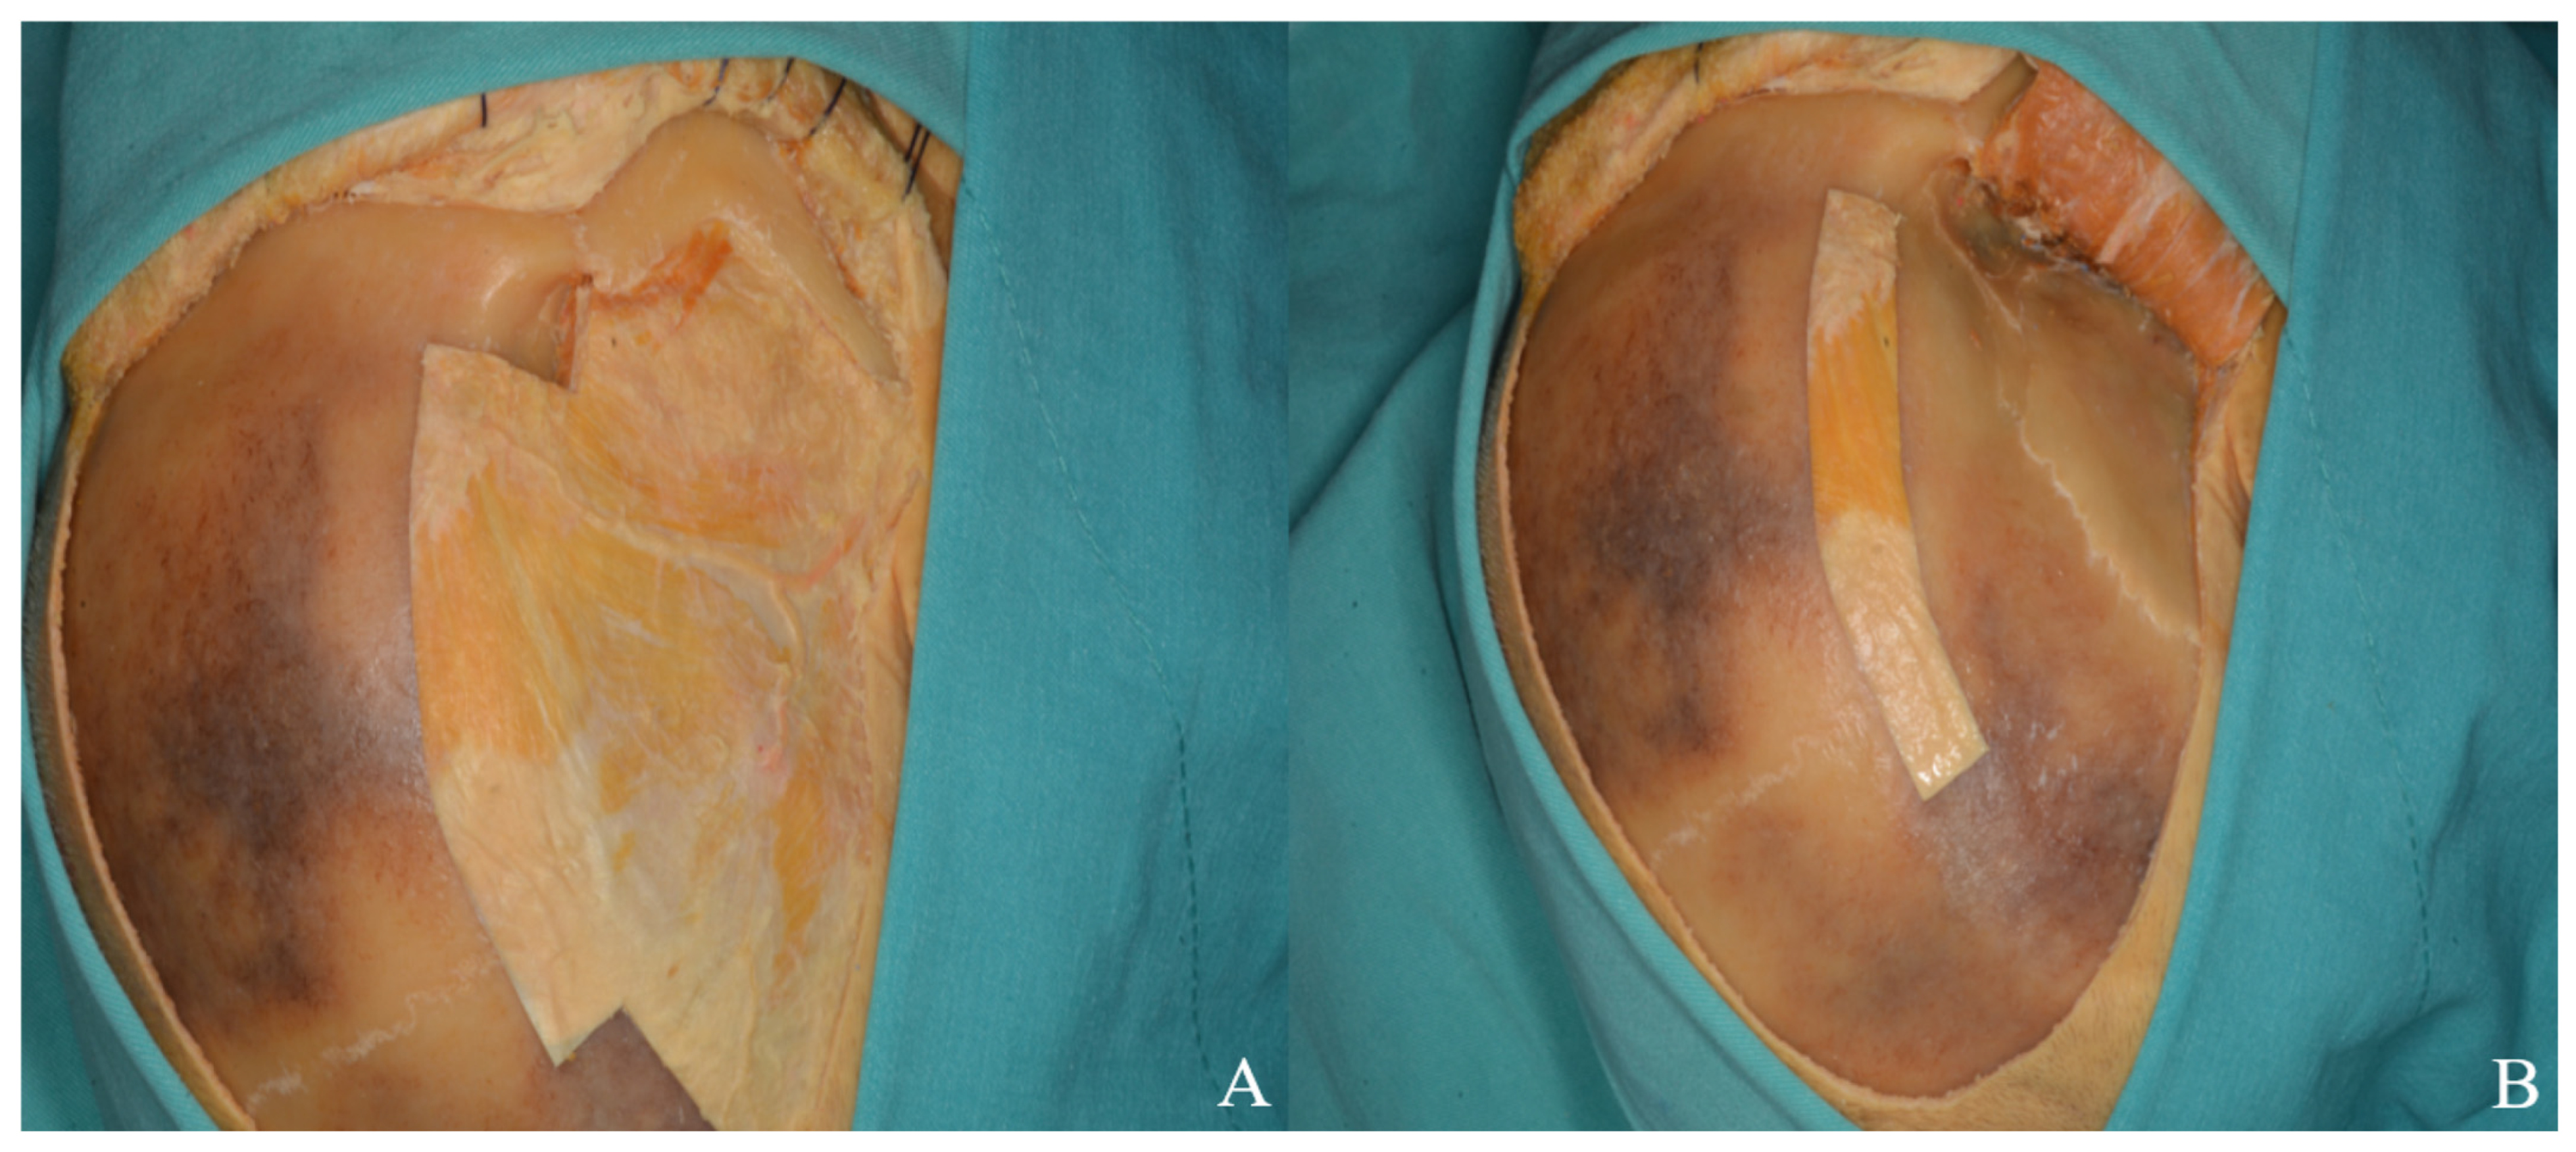

3.2.4. Craniotomy

3.2.6. Dura Incision and Sylvian Fissure Opening